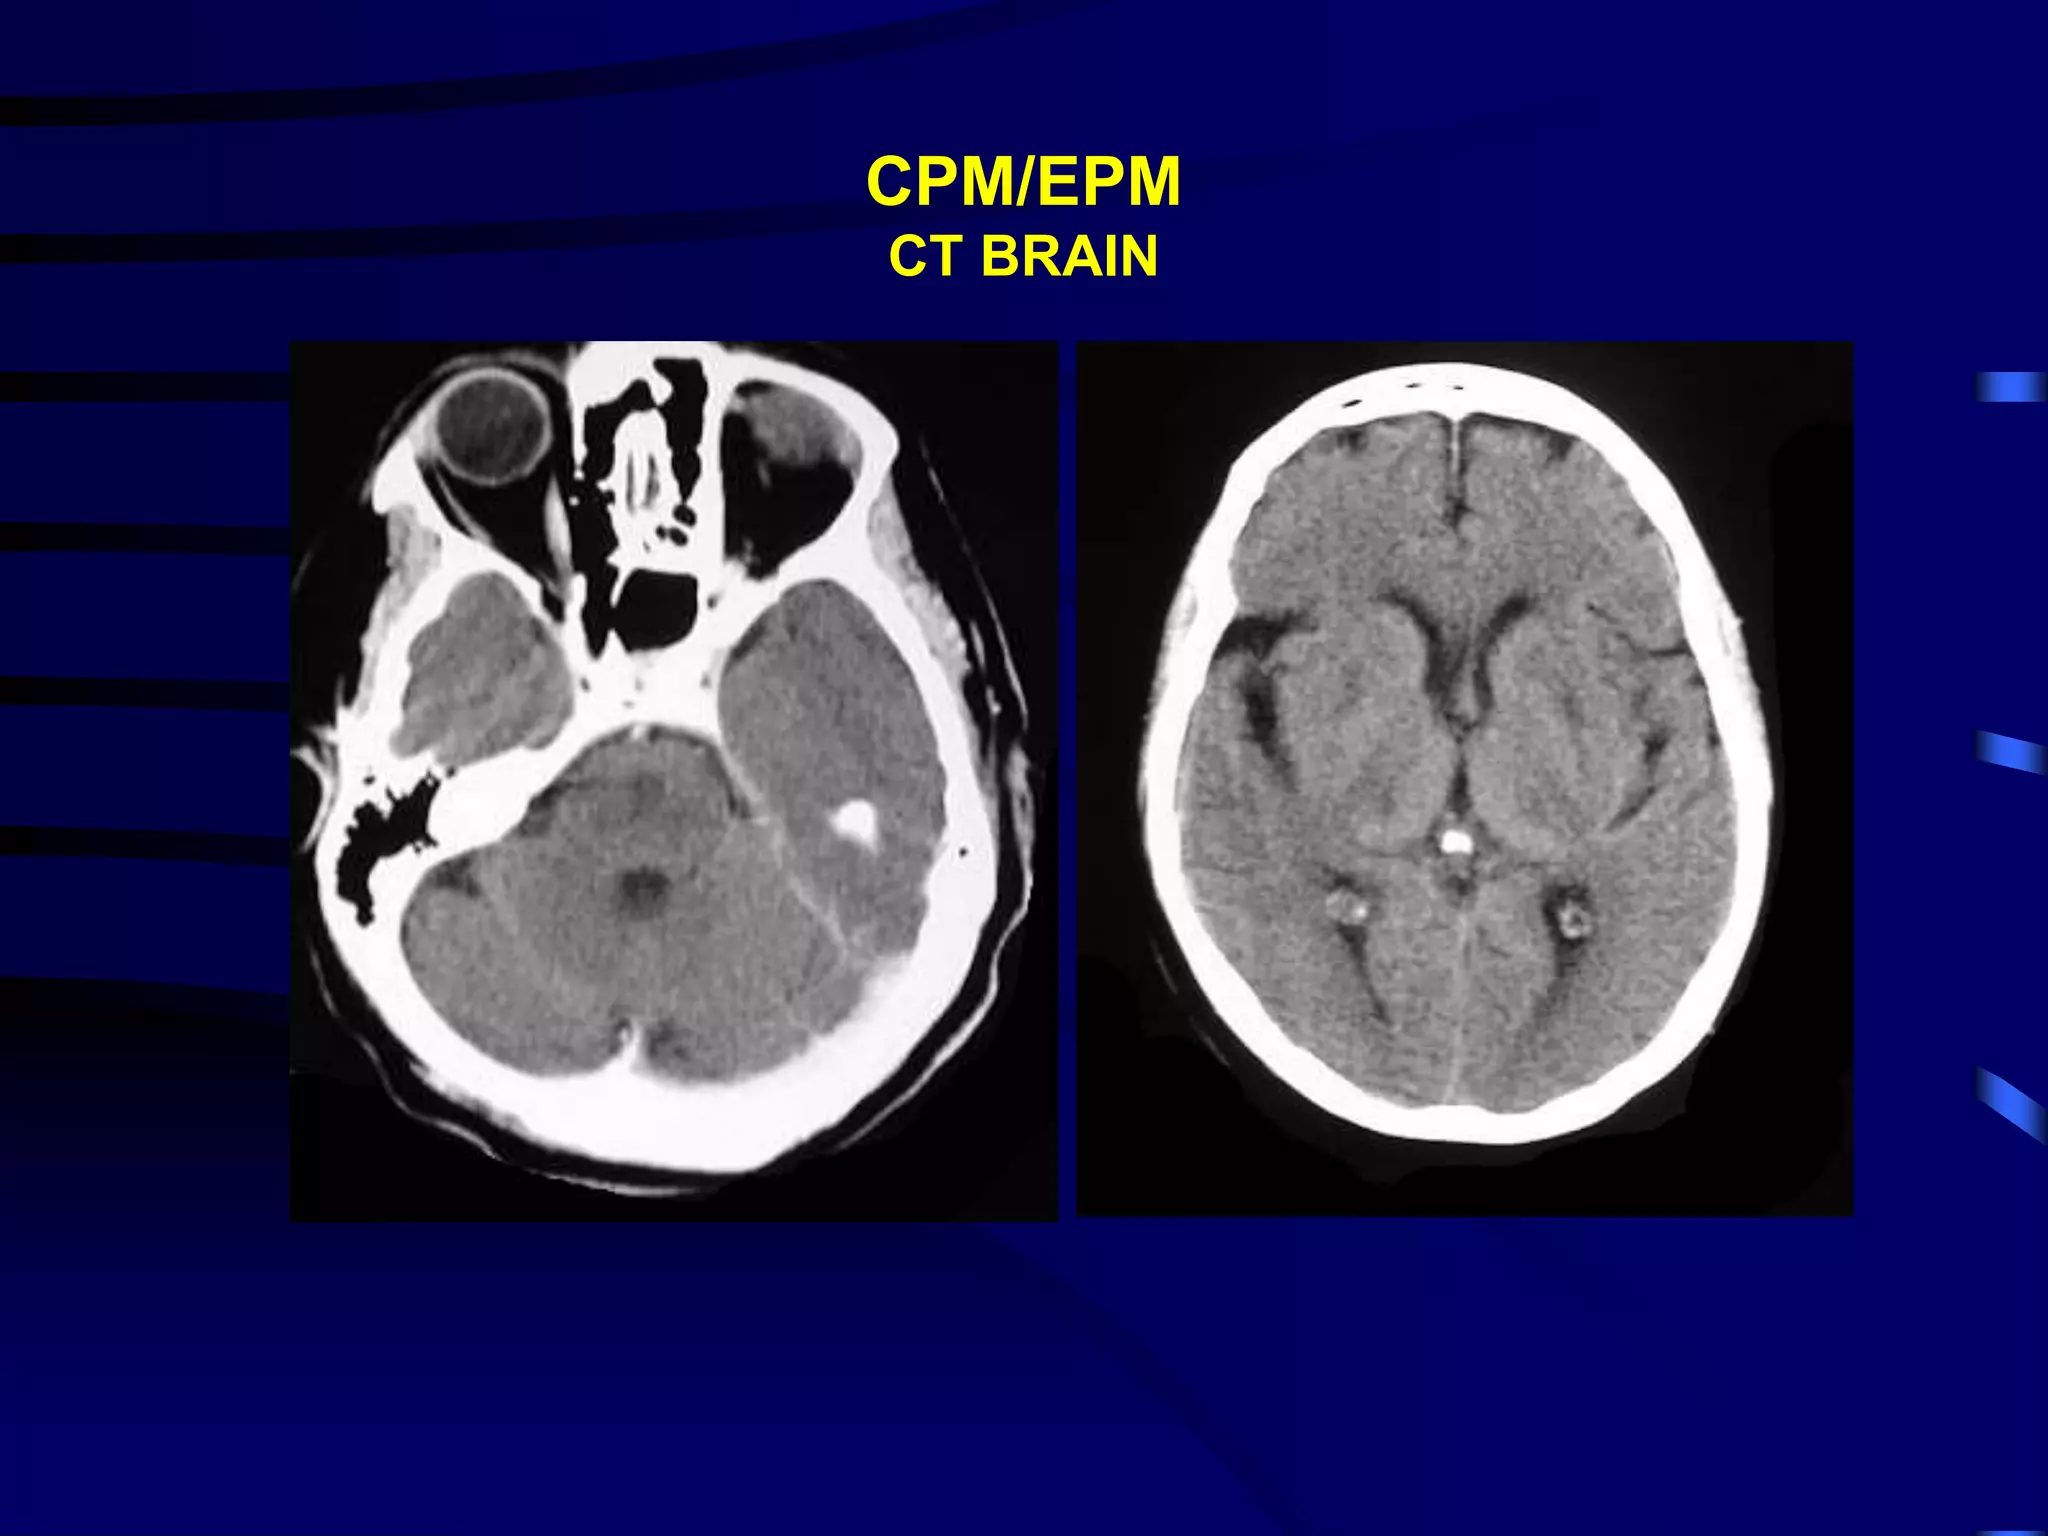

PONTINE/EXTRAPONTINE MYELINOLYSIS

• Characteristic symmetrical demyelination of central portion of

the base of the pons

• Clinical features CPM: spastic paraparesis/tetraparesis,

pseudobulbar palsy (dysphagia, dysarthria, mutism, emotional

lability, locked in syndrome, bilateral/unilateral abducens palsy,

conjugate gaze palsies; altered mental status; Horner’s

syndrome

• Sites of EPM: cerebellum, cerebral peduncles, lateral geniculate

body, thalamus, lentiform nuclei, caudate & internal capsule and

cerebral white matter

• EPM: extrapyramidal signs, cerebellar ataxia, dystonia;

behavioural abnormalities

PONTINE MYELINOLYSIS

CPM/EPM

CT BRAIN

EXTRAPONTINE MYELINOLYSIS

Cerebellum

Caudate & Lentiform

nuclei